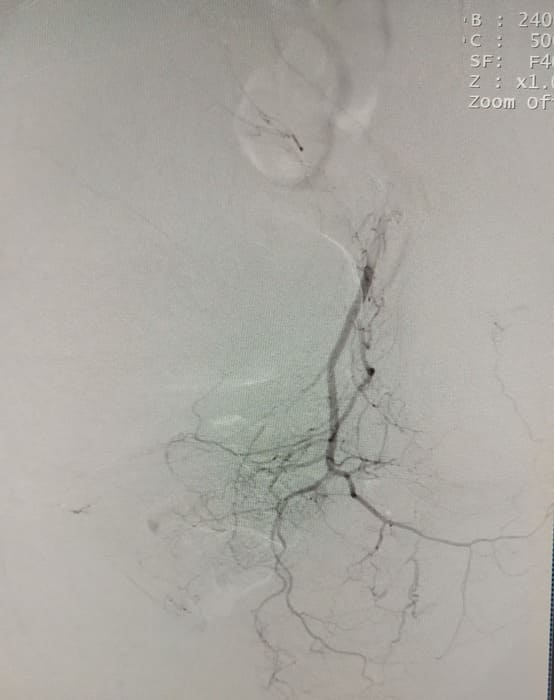

Зазвичай люди літнього віку мають вражені атеросклерозом та звивисті, внаслідок гіпертонічної хвороби судини. Цей випадок не був виключенням, тому нам довелося докласти максимум зусиль, використати високотехнологічне обладнання та інструменти, щоб віднайти цільові судини. На диво, незважаючи на попередню операцію, судинний малюнок рецидивної простати збігався з тим який буває у не оперованих пацієнтів. Тому нам вдалося їх чітко визначити з обох сторін та заповнити емболами. Це доволі кропітка праця, адже щоб викликати ішемію, необхідно поступово виключити кровоплин в усій тканині залози. Полегшувало операцію лише відсутність перетоків артерій на сусідні органи. Це дозволило нам безпечно емболізувати, не боячись негативних наслідків та ускладненнь.

Операція була виконана 28.05.2021. під місцевою анестезією, доступом через прокол в правій стегновій артерії. Вже на протязі тижня зменшилась кількість походів в туалет по маленькому (вночі до 1 разу), полегшилось сечовиділення та покращилось самопочуття хворого.